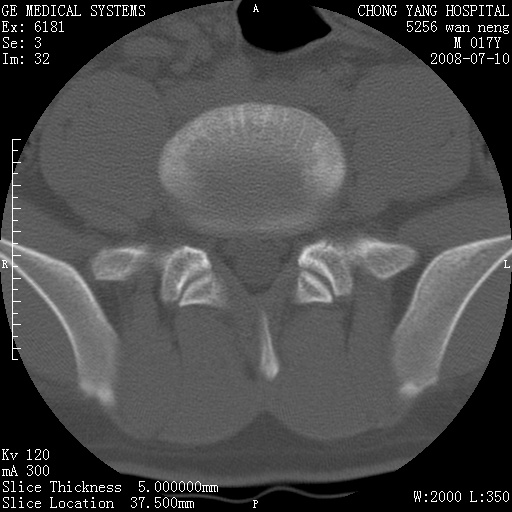

腰3、4椎弓崩裂

腰3、4椎弓不连

支持:腰3、4椎弓峡部崩裂。

腰3、4椎弓峡部不连

支持:腰3、4椎弓峡部崩解。

腰3、4,如受过外伤则为陈旧骨折,否则为骨质不连

图片漂亮,目前也只能看到腰3、4骨质不连

腰3、4椎弓峡部裂。

腰3、4椎弓峡部裂。支持

重建图像见多个椎弓峡部不连(不足为据),平扫未见异常。

支持腰3、4椎弓峡部崩裂。